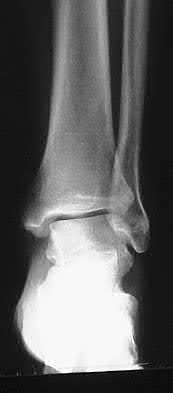

A 34-year-old male sustains the closed injury seen in Figure A as a result of a high-speed motor vehicle collision. What is the most appropriate next step in treatment?

The radiograph shows a comminuted pilon fracture, which is associated with high-energy trauma and significant soft tissue injury. The tested concept here is the importance of avoiding definitive reduction and fixation of this high-energy injury, which has been shown to be associated with an increased risk of wound complications and deep infections (as compared to staged treatment with usage of a spanning external fixator).

Patterson et al. reviewed 23 consecutive patients with comminuted distal tibia fractures. They showed 0% infections or wound-healing problems in their patient population treated with a two-staged protocol. Their protocol involved fibula fixation with an intramedullary implant and application of a medial external fixator to to regain length and restore anatomic alignment. Reevaluation of the limb occurred ten to fourteen days later for definitive fixation.

Sirkin et al. retrospectively reviewed 40 closed and 17 open pilon fractures (AO types 43A-C) that were treated with staged surgical management (avg. time from ext. fix. to formal reconstruction was 14 days (range 4 to 31) They reported 17% post-operative wound complication in the closed group and 11% post-operative wound complication in the open group (Gustilo Type I-III). They suggest the technique was successful in both closed and open pilon fractures.